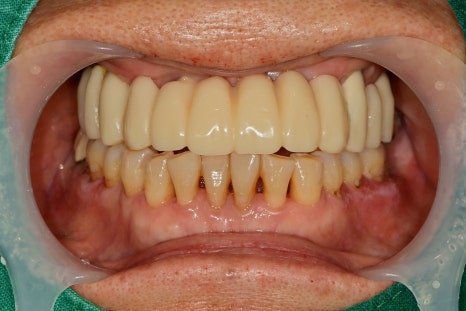

오랜 기간 치료가 끝이 났습니다.

치료 후 환자분께서 씹는 것이 아주 좋아졌다고 하십니다.